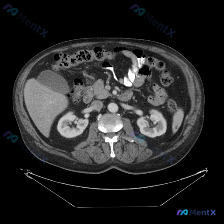

最近看到一份有意思的影像资料,不是因为发现了典型病变,而是恰恰相反——预设了“脾脏病变”的问题,但图像里却找不到明确异常。整理一下思路分享给大家。 --- 一、先看影像信息(单帧上腹部CT软组织窗横断面) 直接说客观看到的: 1. 肝脏:轮廓尚平滑,肝叶比例正常,实质密度大致均匀,肝内血管走形正常,...

整理了一个很有警示意义的影像读片场景,特别能体现「循证影像诊断」的重要性。 先看「预设问题」与「影像事实」的冲突 预设: 临床/提问指向「图中存在脾脏病变」 影像事实(单帧增强CT): - 扫描层面:仅上腹部,显示肝右叶部分、胆囊、双肾、胰腺、血管、胃及肠管 - 强化状态:增强扫描(血管强化明显),...